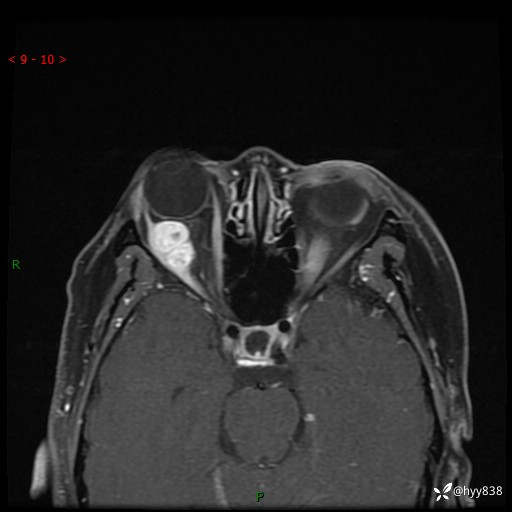

老年女性,右眼球突出1月。说说鉴别诊断,看谁第一个秒---(有结果)

主诉:发现右眼球突出1月余

简要病史:患者于1月前无明显诱因发现右眼球突出,偶感磨痛、眼胀,无视力下降,无头痛,恶心呕吐等不适。10天前就诊于当地县人民医院就诊,完善头颅ct检查,诊断为右侧眼眶肿物,建议患者上级医院进一步治疗,患者因个人原因拒绝。拟行手术,来我院就诊,门诊行相关检查后以“右眼眼眶肿物”收入院。 患病以来,患者精神饮食睡眠尚可,大小便如常、体重无明显改变。

辅助检查:MRI

临床诊断:眼眶肿物

眼眶MRI平扫+增强